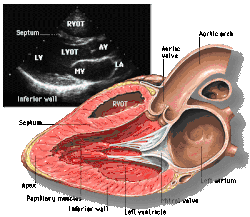

![]() Subcostal four chamber | ![]() Apical four chamber | ![]() Parasternal long axis | ![]() Parasternal short axis | ||||||||

Each figure contains a TTE with a black background, and a corresponding colored illustration. | Patrick J. Lynch and C. Carl Jaffe, Yale University, 2006. | ||||||||||

Click on a figure to enlarge it and see some parts of the heart identified. RV, right ventricle; LV, left ventricle; RA, right atrium; LA, left atrium; TV, tricuspid valve; MV, mitral valve; AV, aortic valve; RVOT, right ventricular outflow tract; LVOT, left ventricular outflow tract |